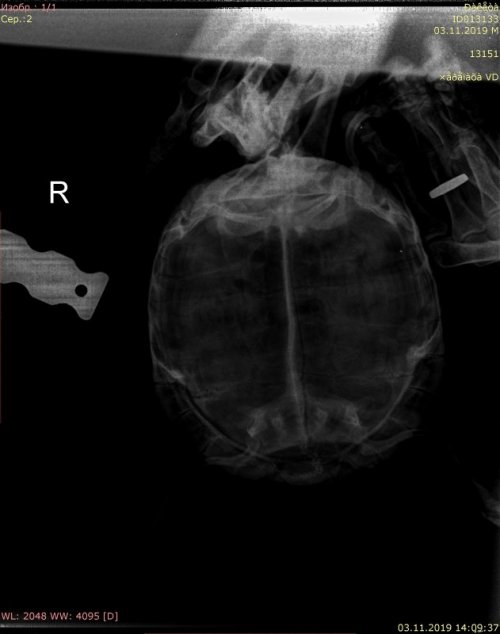

сделайте рентген в вентро-дорсальной проекции (пластроном лёжа)

Рентген нужен для исключения яиц, т.к. гиперактивность часто проявляется у самок, готовящихся к кладке. Яйца могут образовываться и без самцов. Рентген покажет есть/нет и если есть, то размеры, как расположены и есть ли риск дистоции. Задержка кладки у черепах это состояние, которое нельзя допускать.

Рентген должны сделать в любой ветклинике с рентгеном, настройки для этого на сайте есть, если вдруг в клинике сомневаются как делать https://cherepahi.ru/care/zdorove-cherepax/164-rentgen-dlya-cherepax-kak-gde-delat-kak-ponimat

@TorToise @moth @Цветик @Podolnyi Я сделала рентген, прикладываю к комментарию. Клюв тоже подрезали. Посмотрите, пожалуйста

02838649-1B7F-44DA-B0CC-D80B13D64F8B.jpeg

0B9CFFE3-E3DB-4F6D-86E4-6EC1C3C833F6.jpeg

@Бухман Лиля Не разбираюсь в болезнях и лечении черепах, но, по-моему, яиц на рентгене не видно.